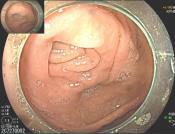

• EyeMax洞察胆胰管成像系统辅助内镜逆行阑尾炎治疗术的疗效及安全性分析

摘要:目的 探究一次性eyeMax洞察胰胆管成像系统辅助内镜逆行阑尾炎治疗术(ERAT)治疗阑尾炎的效果及安全性。方法 回顾性分析2023年4月-2024年9月在该院就诊,通过影像学或内镜检查确诊的54例非复杂性阑尾炎患者的临床资料。所有患者均行eyeMax洞察胆胰管成像系统辅助ERAT,于直视下观察阑尾腔,并通过冲洗、取石、扩张狭窄和支架引流等措施治疗阑尾炎。观察手术相关指标、术后疼痛程度、并发症发生情况、术后1年内复发率、结肠镜下表现、胰胆管成像系统下表现和胆胰管成像系统下治疗情况。结果 54例患者均顺利完成手术,技术成功率为100.0%,手术时间(60.6±27.9)min,住院时间(3.6±1.5)d;30例(55.6%)阑尾开口及周边黏膜充血水肿,2例(3.7%)可见脓液及污秽物流出;54例(100.0%)患者阑尾腔内壁充血水肿,51例(94.4%)可见腔内絮状物、脓液或脓苔附着,25例(46.3%)可见腔内粪石,15例(27.8%)可见管腔走形迂曲或狭窄。所有患者予以eyeMax洞察胰胆管成像系统治疗,简单灌洗54例,网篮取石20例,支架引流25例。术后VAS评分为0(0,0)分,明显低于术前的6(3,7)分,手术前后比较,差异有统计学意义(Z = -6.24,P = 0.000)。所有患者术后症状均暂时缓解,术中及术后未发生穿孔和大出血等严重不良事件。随访1年内,阑尾炎复发率为20.4%(11/54)。结论 EyeMax洞察胆胰管成像系统辅助ERAT是治疗非复杂性阑尾炎安全和有效的疗法,其具有直视下精准操作、保留阑尾功能、症状快速缓解、无X线暴露和精准诊疗阑尾病变等优势。值得应用于临床。